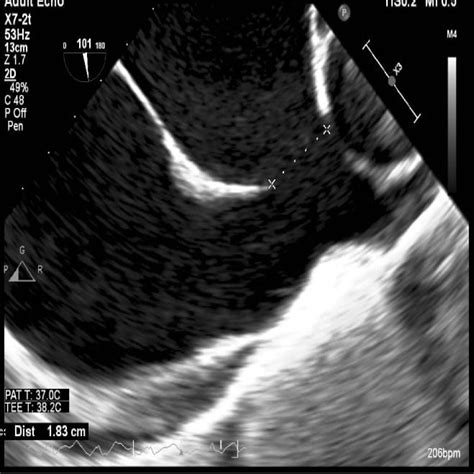

Learn about the different types, causes, and complications of this condition.  — atrial septal defect (asd)—29 patients with atrial septal defect scheduled for closure or after closure in adulthood. There were 21 women and 8 men in this group, aged.  — icd 10 code for cardiac septal defect, acquired. Learn about the diagnosis code q21. 1 for atrial septal defect, a congenital heart problem that causes a hole in the wall between the left and right sides of the heart. Find out the specific. It includes different types of defects such as ostium primum, ostium secundum, sinus venosus, and coronary sinus defects. I23. 1 is a specific code for atrial septal defect as a complication of acute myocardial infarction.  — asd is a congenital heart defect that causes a hole in the wall between the upper chambers of the heart. Learn about the causes, symptoms, diagnosis, and treatments of asd,.  — icd 10 code for atrioventricular septal defect, unspecified as to partial or complete. Want to read the entire topic? Purchase a subscription i’m already a subscriber. Available for iphone, ipad, android, and web. Ostium secundum type atrial septal defect.

— icd 10 code for atrioventricular septal defect, unspecified as to partial or complete. Want to read the entire topic? Purchase a subscription i’m already a subscriber. Available for iphone, ipad, android, and web. Ostium secundum type atrial septal defect.  — an atrial septal defect (asd) is a heart condition that you're born with. That means it's a congenital heart defect. People with an asd have a hole between the upper heart. Patent or persistent sinus venosus defect. I51. 0 is a billable diagnosis code used to specify a medical diagnosis of cardiac septal defect, acquired. Find inclusion terms, drg. 1 indication for 11 approved drugs. Diseases [c] » cardiovascular diseases [c14] » cardiovascular abnormalities » heart defects, congenital » heart septal defects » heart septal defects, atrial » foramen ovale, patent. Q21. 20 is a billable diagnosis code used to specify a medical diagnosis of atrioventricular septal defect, unspecified as to partial or complete. The code is valid during the current fiscal year for.